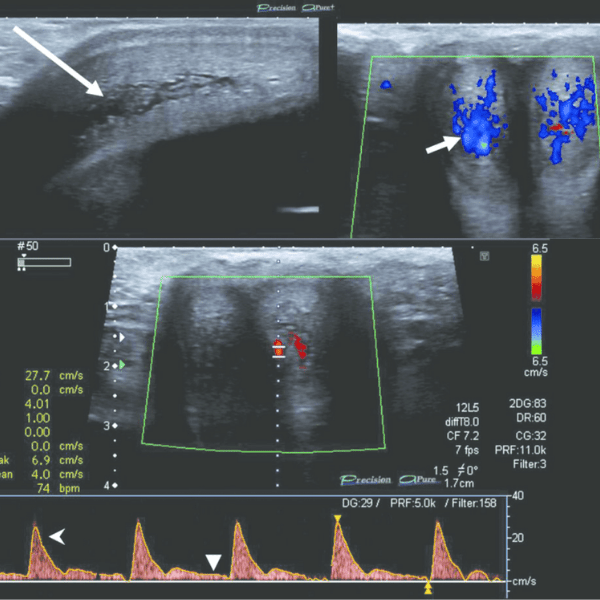

Ở dương vật, siêu âm doppler sẽ giúp đánh giá cấu trúc của mô mềm xung quanh dương vật, sự liên tục của bao trắng dưới da và sự đồng nhất của thể hang hai bên. Bên cạnh đó, siêu âm doppler còn giúp đánh giá sự lưu thông mạch máu trong dương vật nhằm giúp các bác sĩ xác định nguyên nhân những trường hợp cương dương vật kéo dài hoặc giúp chẩn đoán tình trạng rối loạn cương do bệnh lý mạch máu gây ra như: hẹp hoặc xơ vữa động mạch dương vật.

Không chỉ vậy, sự hỗ trợ của siêu âm doppler còn giúp phát hiện ra những bệnh lý liên quan đến mạch máu như: giãn tĩnh mạch thừng tinh, thiếu máu nuôi tinh hoàn do xoắn tinh hoàn (xoắn thừng tinh) hoặc tình trạng viêm nhiễm ở tinh hoàn. Ngoài ra, siêu âm bẹn bìu còn giúp phát hiện sớm những bệnh lý ở bẹn, đặc biệt là thoát vị bẹn ở nam giới.